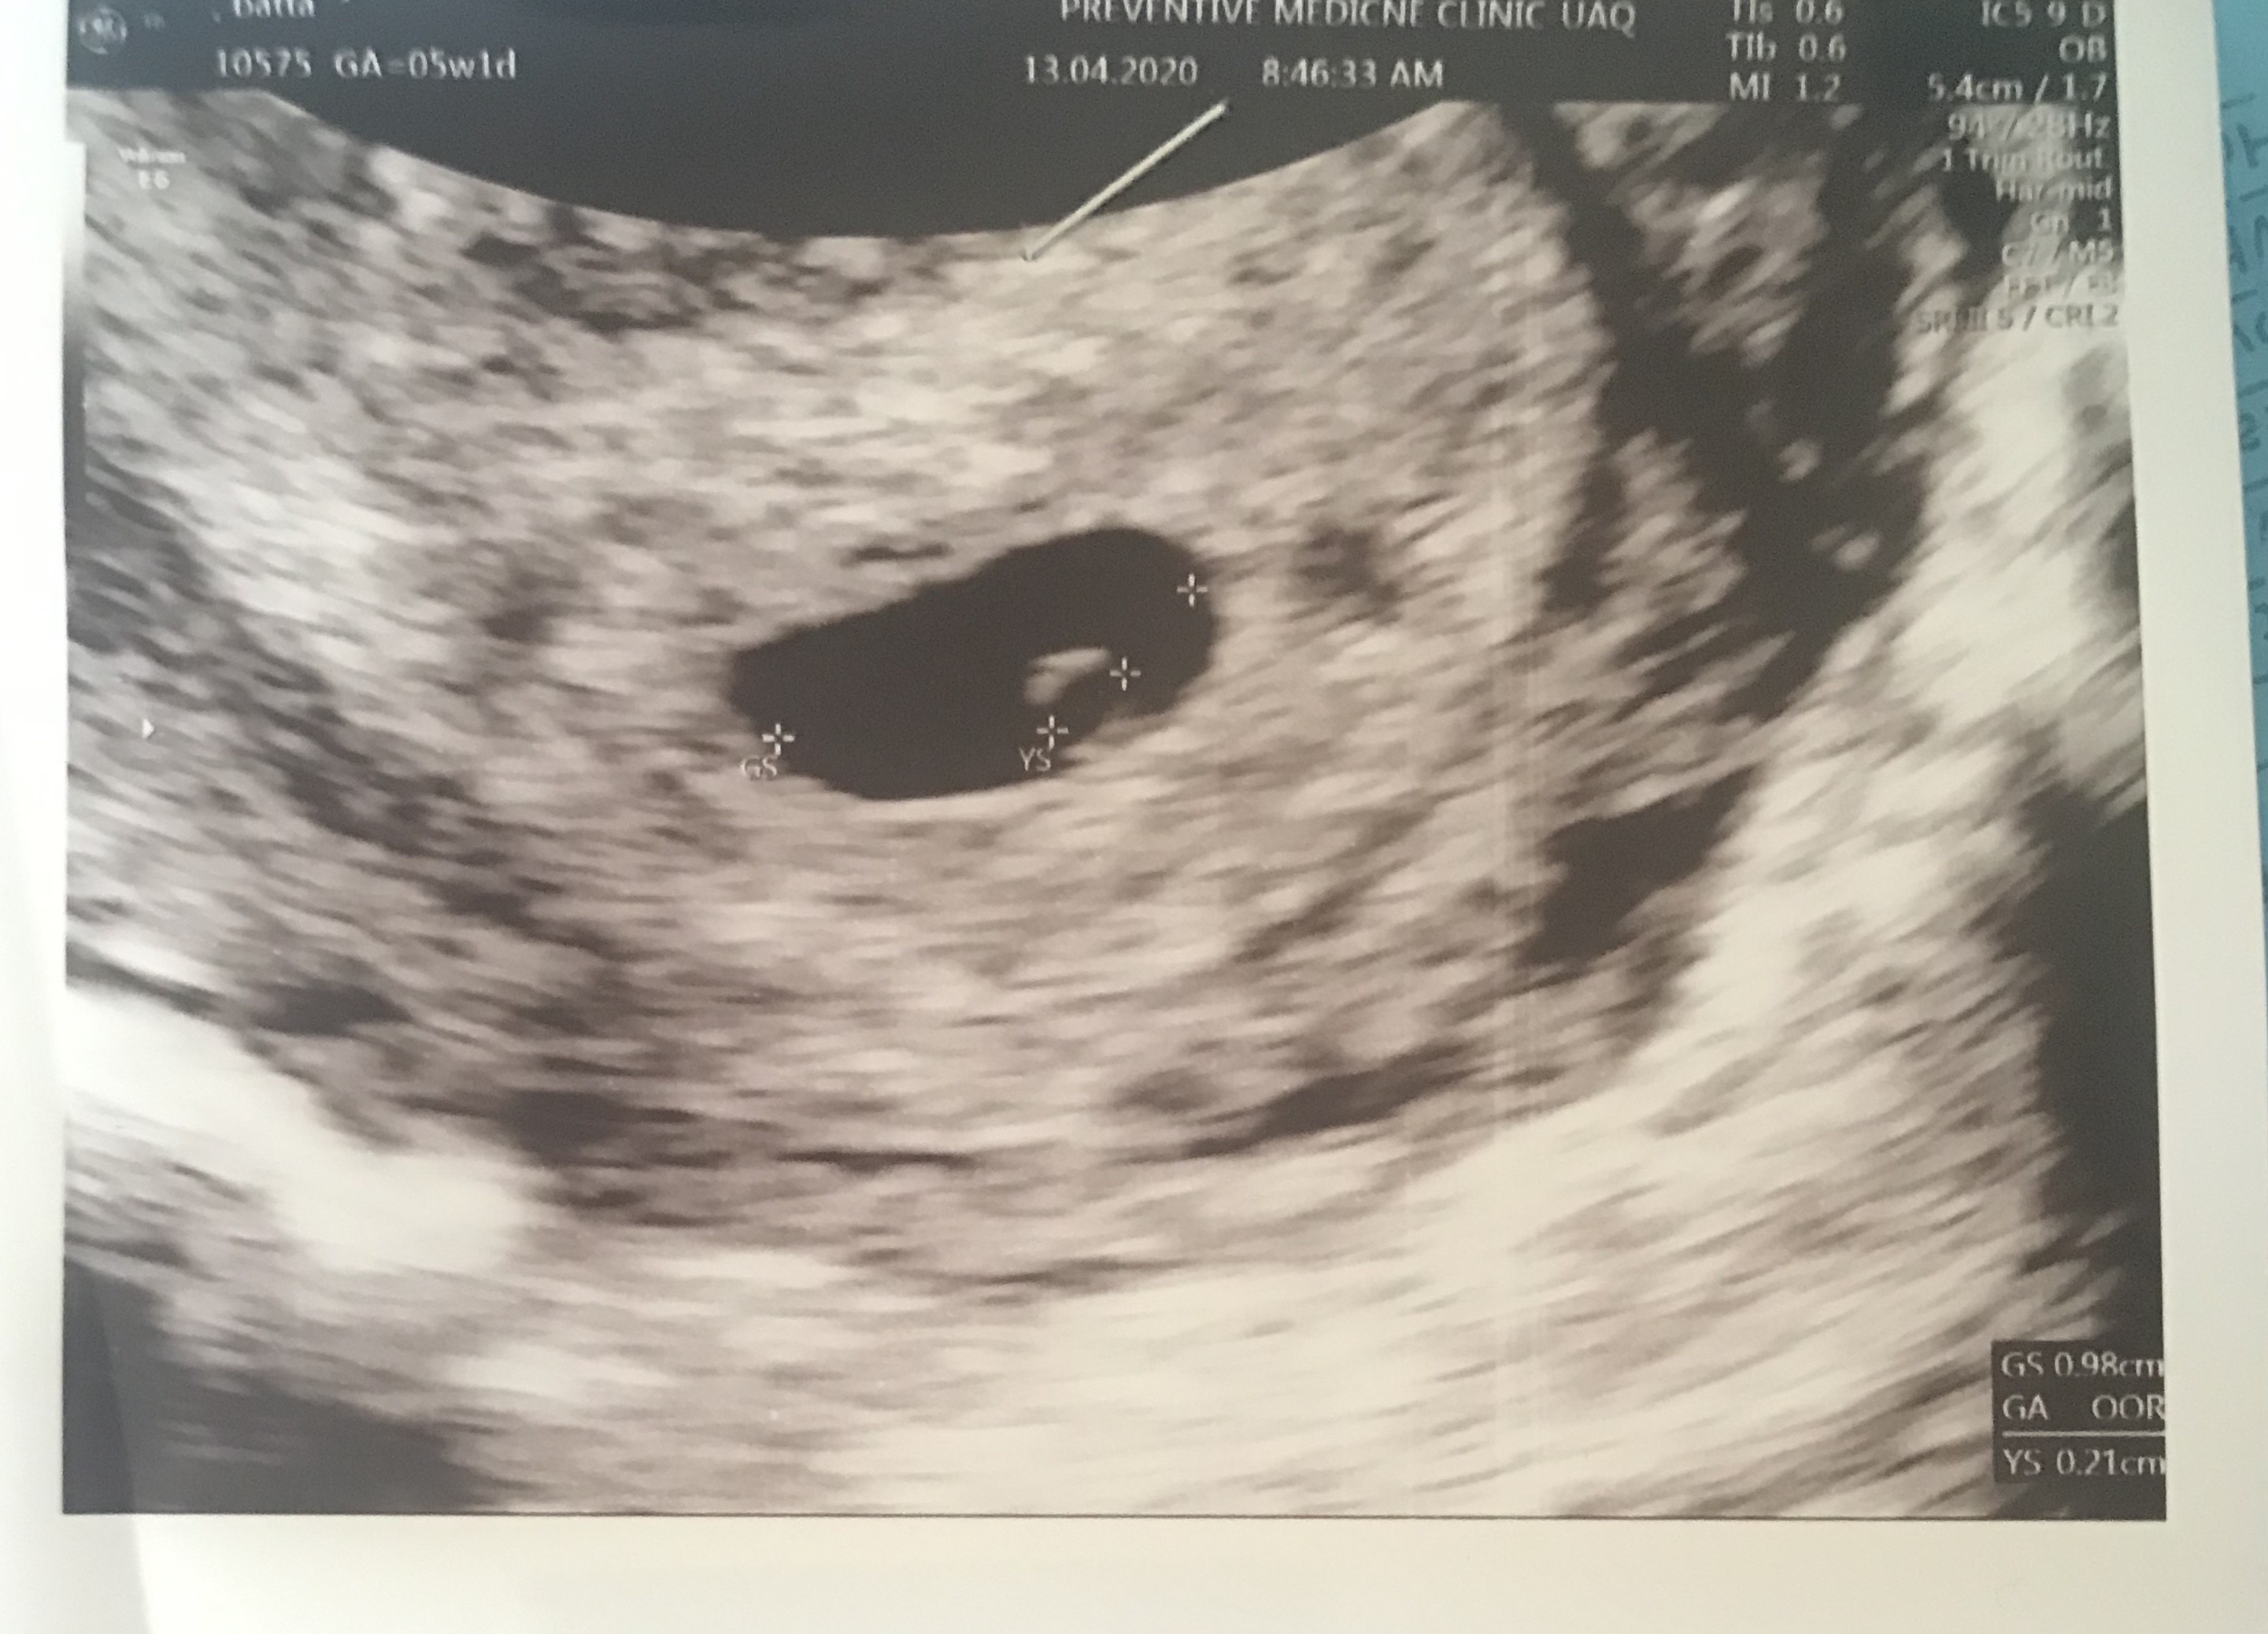

Hej dziewczyny czy wy tez miałyście mały pecherzyk zoltkowy lekarz powiedział ze jest za mały 🤷‍♀️Z OM 5t1d z usg nie mogła określić wieku ciążowy ok ??. Załączam usg

• 3EE8AFC0-230F-47BA-8CF1-EE5B68DEFB06.jpeg

3EE8AFC0-230F-47BA-8CF1-EE5B68DEFB06.jpeg